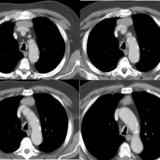

Case 8c Thymoma CT